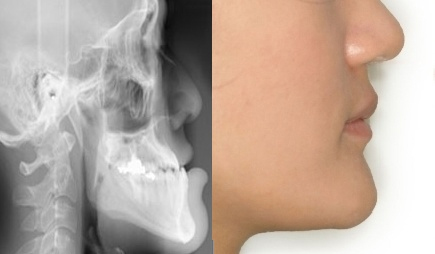

올 해 중학교에 입학한 아들을 둔 최모씨는 치아교정 때문에 고민이다. 주걱턱으로 아래 치아가 위 치아를 덮고 있는 부정교합이 심해 초등학교 4학년부터 교정을 시작한 최씨의 아들이, 턱이 계속 비뚤게 자라고 치아의 중심선도 잘 맞지 않게 되자 ‘치아교정도 소용없다’며 자주 거울을 보며 속상해 하고 있기 때문이다. 교정을 담당했던 치과에서도 ‘지켜보자’는 말 외에 더 이상의 치료는 중단한 터라 아들의 상실감은 더욱 큰 상태. 사춘기에 접어 들면서 외모에 대한 관심이 더욱 커진 아들의 턱 수술을 심각하게 고민하고 있는 그녀가 주의할 점은 없을까? 김재승교수(건국대학교병원 치과)는 “턱뼈 자체에 문제가 있을 시, 더 이상의 무리스러운 교정치료는 시도하지 않는 것이 좋다.”고 조언한다. 교정을 담당했던 치과 의사의 말을 따르는 것이 옳다는 것. 턱교정 수술은 골격에 관한 수술이므로 초등학교 때 주걱턱이 발견된 경우, 교정 치료로 효과가 없으면 아무 것도 하지 않고 있다가 얼굴 골격의 성장이 완료된 18세 이후에 수술을 하는 것이 효과적이라고 한다. 수술이 가능한 나이가 되면, 턱교정 수술을 전문으로 하는 병원과 수술 케이스가 많은 의사를 찾아 정확한 상담과 진단을 받은 후 자신에게 맞는 치료방법을 찾는 것이 좋다. 수술로 치료해야 하는 주걱턱의 경우 각 개인이 지닌 턱뼈와 치열의 특징을 분석하여 치료과정을 수립하는 것이 수술 후 부작용을 줄이는 데 가장 중요한 역할을 하기 때문이다. 턱수술에 있어서 정확한 진단만큼 중요한 것이 정밀한 진단이다. 골격의 이동이 가해지는 수술이므로 얼굴의 입체적인 분석이 기본이 되어야 하는데, 얼굴 내부 뼈의 해부학적 구조를 파악, 보다 안전하고 정확한 수술을 가능하도록 해 주는 3D CT(3차원 영상분석)를 활용하면 출혈이나 수술에 따른 여러 부작용을 최소화 할 수 있다고 한다. 또한 전신마취가 행하여지는 수술인 만큼 마취과 전문의가 상주하는지 확인하는 것이 중요하다. 보다 안전한 수술을 위해서는 구강악안면외과와 마취과, 교정과 전문의의 진료를 한 공간에서 받을 수 있는 병원 및 응급 시 협진 진료 체계가 가능한 종합병원에서 수술을 받는 것이 안전하고 만족한 결과를 얻는 데 효과적일 수 있다. 마지막으로 주의할 것은 치아교정으로 효과를 보지 못했다고 해서 교정치료에 대한 불신을 가져서는 안 된다는 것이다. 주걱턱 수술의 경우 치아의 저작기능과 밀접한 관련이 있는 수술이므로 대부분 교정이 수반되어야 한다. 간혹 저작기능에 큰 문제가 없었던 환자들 중 긴 시간을 요하는 교정치료의 필요성에 의문을 제기하는 경우가 있다. 하지만, 턱교정 수술이 턱뼈를 움직이는 수술인 만큼 정상적인 저작기능을 위해선 교정치료가 꼭 필요하다고 할 수 있다. 선수술이 가능한 경우라도 수술 후 세밀한 치열과 정상적인 기능을 위해 교정을 해 주는 것이 만족한 결과를 얻는 데 도움을 준다는 점을 잊지 말아야 한다. [OSEN=생활경제팀]osenlife@osen.co.kr 주걱턱수술이 필요한 환자의 증례(건국대 병원 김재승 교수 제공)